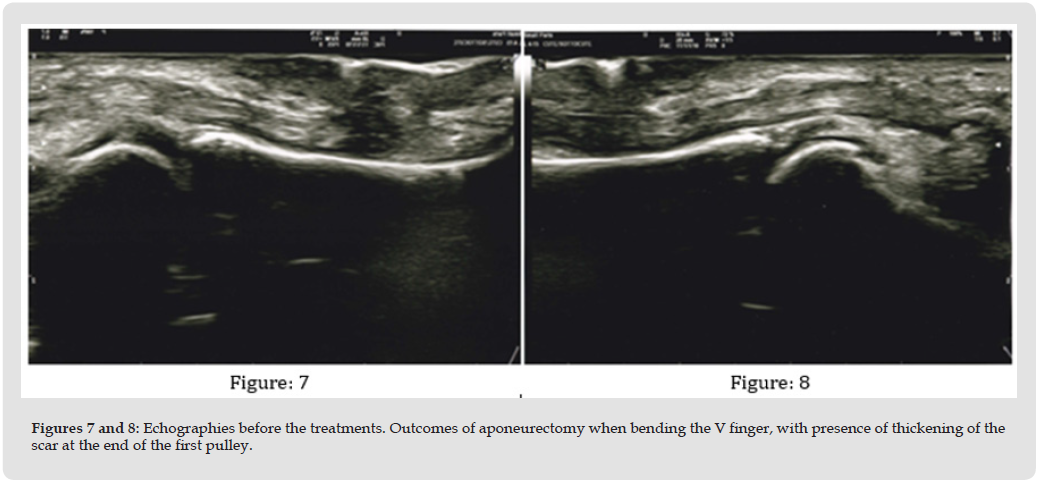

All patients responded positively to the therapy, showing an increased extension of the treated fingers and a softer and more elastic tissue from the very first treatment application. The echographies showed a reduction in the thickening of the scar and its fibrosis combined with an increased cleaving of the tendon structures. The infrared camera detected a significant difference between the maximum temperature of the fingers (36.4 °C) and the retracted finger, which average temperature was 34.8 °C before therapy. After the treatment cycle, the maximum temperature of the hand was stable (36.5 °C) while that of the suffering finger increased to 35.6 °C, demonstrating a more uniform vascularization of tissues. DASH assessment score provided crucial information on functional recovery of the fingers/hands, as before the treatment the average level was 37.33 (from 32.50 to 42.75) while after the cycle of sessions it reduced to an average value of 11.66 (from 6.50 to 16.75), with a significant average improvement of 25.67 (equal to 68.77%).The average comfort level was 7.71 (from 7 to 9), showing that the patients considered the treatment pleasant and relaxing. VAS scale before the treatment cycle showed an average level of pain of 3.01 (from 2.1 to 3.5), after therapy it lowered to an average value of 1.07 (from 0 to 1.8) showing a significant average improvement (-1.94 equal to -64.5%). The follow-ups performed six months later showed a slight improvement of the VAS scale (average value 0.88, minimum 0, maximum 1.5) and stabilization of the DASH score. No subject experienced side effects, not even minor ones, during the treatments and all of them could immediately resume their normal lifestyles without any restrictions.

This study was developed by combining retrospective experiences of the various authors who casually found to have had similar outcomes on patients treated for scars on the palm of the hands, also burdened by Dupuytren’s contracture, and who then retrieve all the documentation provided in this study. The fortuitousness of this discovery hindered the preparation of a study plan with certain parameters for patient enrollment, such as patient splitting into homogeneous groups in order to compare results with greater precision; however, the authors have decided to stick to those parameters in order to recruit a significant number of patients to see if the results obtained will be confirmed on a large scale. The analysis of the collected data is positive and potentially preferable to existing state-of-the-art therapies, at least for the first six months. If on the one hand more sessions are required (in our case we have provided between 3 and 7), on the other the immediate recovery of full activity by the patients, absence of pain, downtime or restrictions to regular lifestyles as well as greater relaxation of the fingers were appreciated already from the first session. A clear improvement of the pathology with total stabilization over six months was proven by all the assessment scales adopted; this makes us optimistic in view of a larger clinical study. The total absence of side effects, already demonstrated by VEMFtherapy in scars treatment [39,43-46] was also appreciated. Analysis of the existing literature suggests that the combined action between electromagnetic fields and negative pressure has an important effect on the remission of fibrosis [39,43] as has also been shown by the separate use of electromagnetic fields, although in different fields [36-38] and negative pressure, which mechanical action promotes a series of reactions in terms of mechanotransduction [21,22,44,45] by converting mechanical stimuli into biochemical signals that activate a series of cascade reactions, reducing the compactness and strength of the fibrous component. In our opinion, the anti-inflammatory action of the electromagnetic fields is particularly relevant, as these lead to an increase in the production of IL-10 anti-inflammatory cytokines 46, analogously to what has been documented with negative pressure [28] (Figures 6-10).